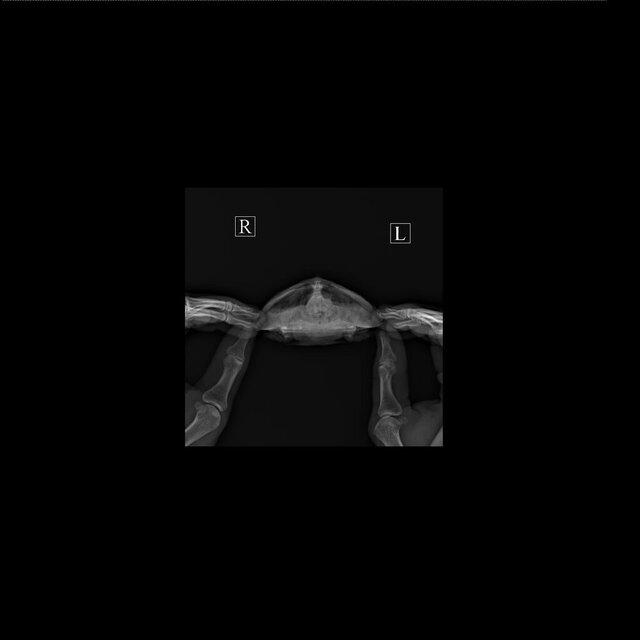

Вы рентген сможете ей сделать? нужен в 3х проекциях. Рентген можно в любой ветклинике сделать где согласятся. Для этого герпетолог не нужен

Сделали рентген. Готовы к онлайн консультации

Есть другой формат рентгена, но сюда не получится выложить

IMG-20230518-WA0002.jpg

IMG-20230518-WA0001.jpg

IMG-20230518-WA0000.jpg